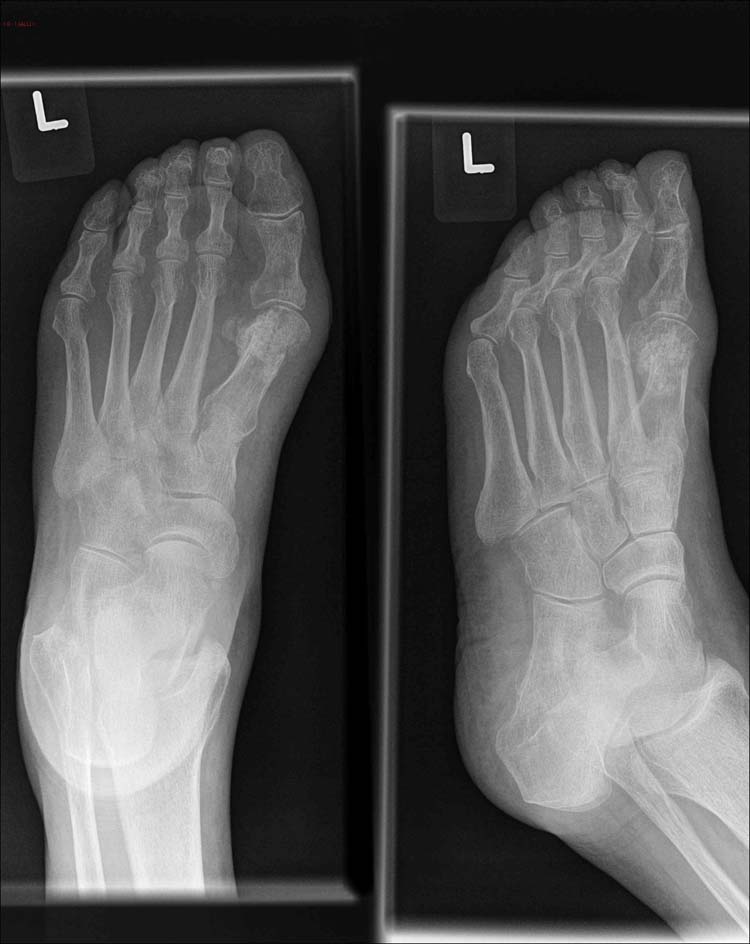

Cool Tricorrectional Bunionectomy 2023. Web bunion surgery is an operation to correct a bunion, which is a deformity of the big toe joint. Tricorrectional bunionectomy j am podiatr med assoc.

Most of them involve repositioning the big toe to. Revisional hallux abducto valgus surgery using tricorrectional bunionectomy Straightening your big toe by removing part of the bone.